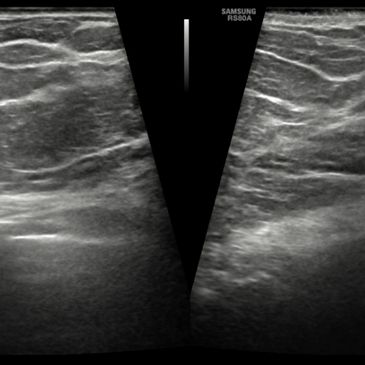

Principle: High-frequency B-mode imaging (7–15 MHz) with real-time assessment of lesion morphology, echotexture, margins, and vascularity.

Indications:

Advantages:

Limitations:

Diagnostic Performance:

Role in Management: